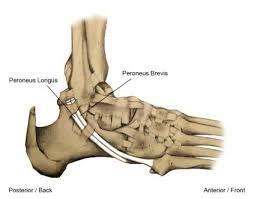

Longus naar brevis transfer

Aan de buitenzijde van de enkel lopen 2 spieren: de peroneus longus en de peroneus brevis. De longus gaat onder de voet door naar de grote teen. De brevis gaat naar de basis van de kleine teen. Vaak is de longus nog sterk en de brevis niet meer. Door de longus door te snijden en vast te maken aan de brevis zorg je voor meer kracht aan de buitenzijde van de enkel/voet en tevens voor een afname van de krachten die de grote teen omlaag trekken (de laatstgenoemde krachten zorgen voor een toename van de holling onder de voet)

Figuur 2: De peroneusspieren. Het litteken komt in de richting van de beide spieren (zwarte streep). De longus snijden we door en hechten we vast aan de brevis.